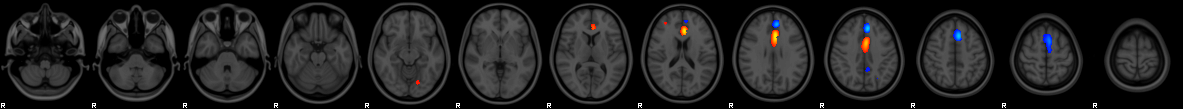

Component #40

Prior:

8% weight

Thickness

:

30% weight

Area

35% weight

VBM

27% weight